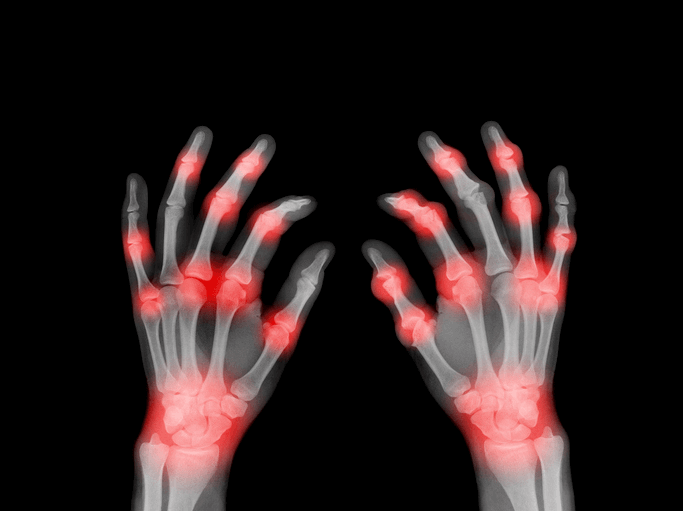

관절 변형: 심한 경우 손가락이 변형되기도 함.

염증성 질환: 류마티스 관절염 등 면역계의 이상 반응.

영상 검사: X-ray, MRI 등을 통해 관절의 손상 정도와 염증 상태를 확인합니다.